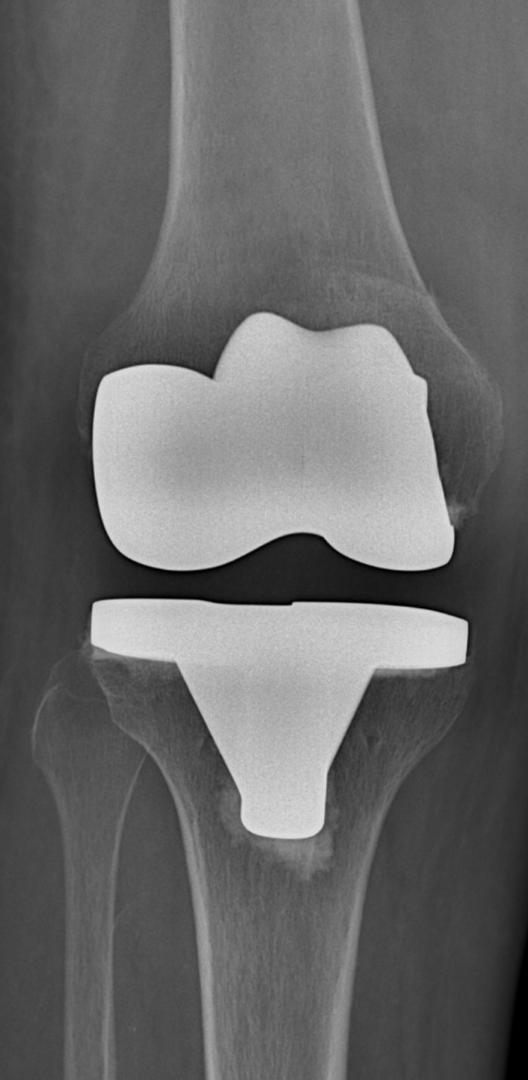

Joint Replacement